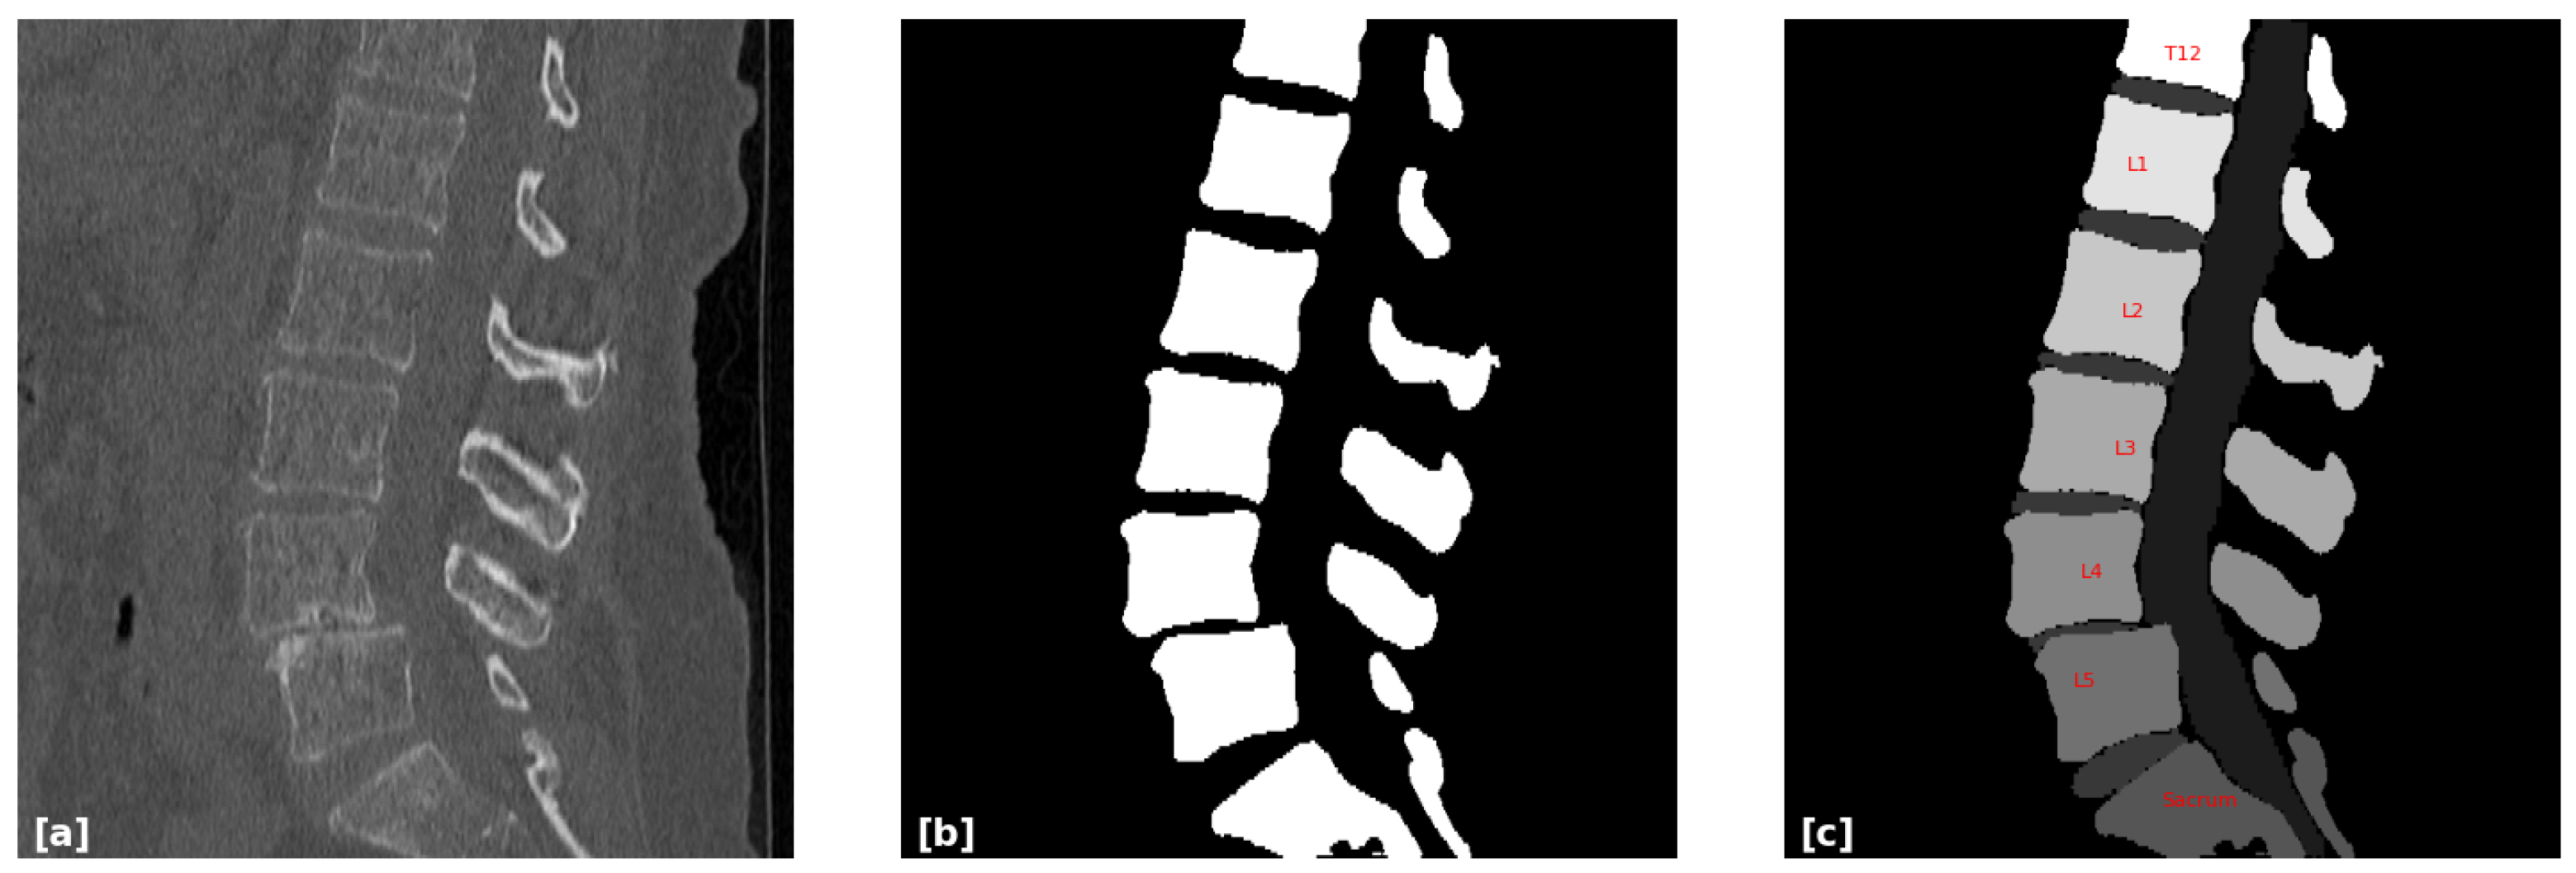

2.2. Three-Dimensional Segmentation and Labeling